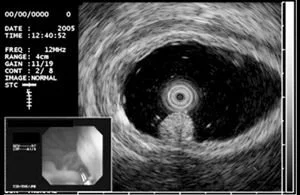

Endoscopic ultrasonography (EUS) allows your doctor to examine your esophageal and stomach linings as well as the walls of your upper and lower gastrointestinal tract. The upper tract consists of the esophagus, stomach and duodenum; the lower tract includes your colon and rectum. EUS is also used to study other organs that are near the gastrointestinal tract, including the lungs, liver, gall bladder and pancreas. Endoscopists are highly trained specialists who welcome your questions regarding their credentials, training and experience. Your endoscopist will use a thin, flexible tube called an endoscope that has a built-in miniature ultrasound probe. Your doctor will pass the endoscope through your mouth or anus to the area to be examined. Your doctor then will use the ultrasound to use sound waves to create visual images of the digestive tract.

EUS provides your doctor with more information than other imaging tests by providing detailed images of your digestive tract. Your doctor can use EUS to diagnose certain conditions that may cause abdominal pain or abnormal weight loss. EUS is also used to evaluate known abnormalities, including lumps or lesions, which were detected at a prior endoscopy or were seen on x-ray tests, such as computed tomography (CT) scan. EUS provides a detailed image of the lump or lesion, which can help your doctor determine its origin and help treatment decisions. EUS can be used to diagnose diseases of the pancreas, bile duct and gallbladder when other tests are inconclusive or conflicting.

EUS helps your doctor determine the extent of the spread of certain cancers of the digestive and respiratory systems. EUS allows your doctor to accurately assess cancer’s depth and whether it has spread to adjacent lymph glands or nearby vital structures, such as major blood vessels. In some patients, EUS can be used to obtain a needle biopsy of a lump or lesion to help your doctor determine the proper treatment.